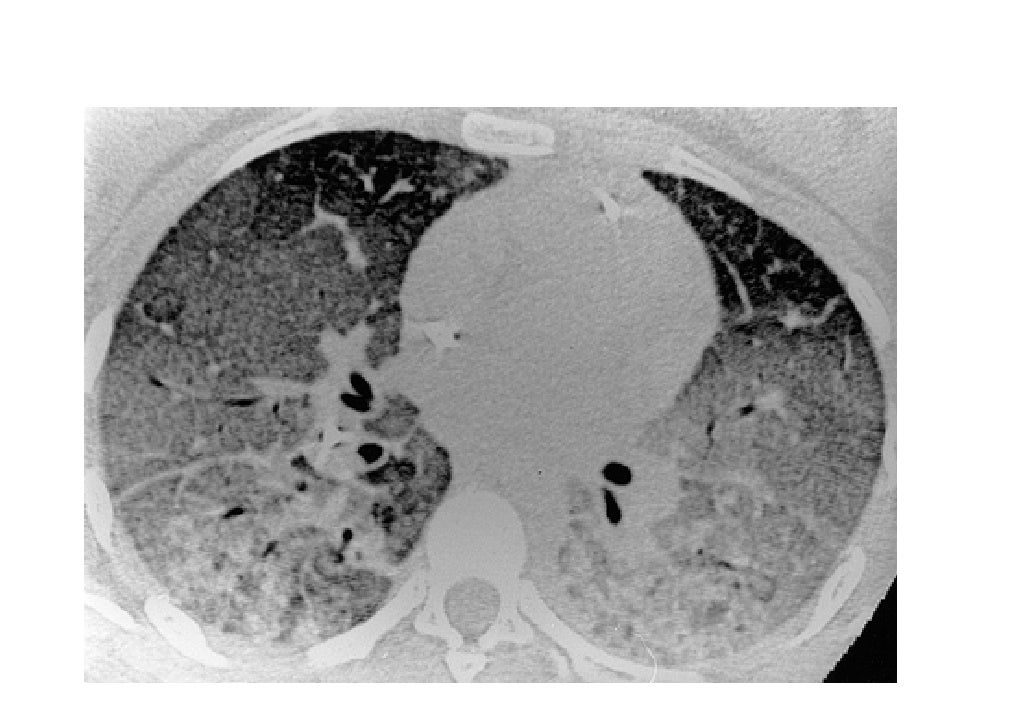

Матовое стекло и консолидация на КТ: диагностика и лечение заболеваний легких